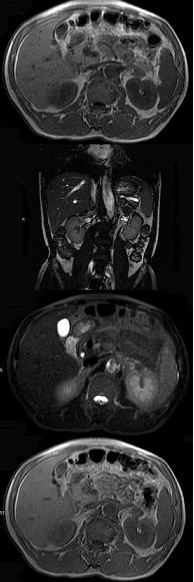

男,52岁,下肢无力伴多饮多尿2年余,实验室检查:低血钾,血醛固酮水平及24小时尿醛固酮定量超过正常值,MRI检查如图所示,应诊断为( )

A:左肾上腺囊肿

B:左肾上腺腺瘤

C:左肾上腺嗜铬细胞瘤

D:左肾上腺髓脂瘤

E:左肾上腺转移瘤